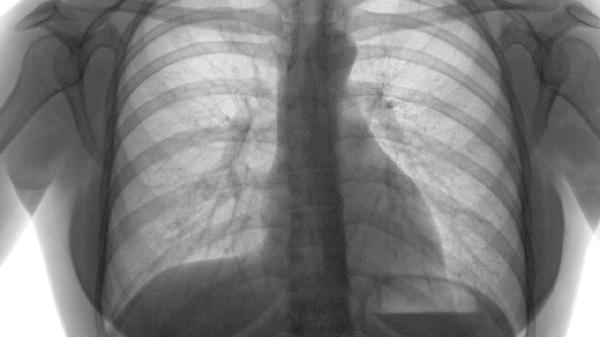

肺气肿片主要用于治疗慢性阻塞性肺疾病(COPD)及肺气肿引起的咳嗽、咳痰、气喘等症状。其主要适应人群包括存在长期吸烟史的中老年患者、职业粉尘暴露人群、反复呼吸道感染者,以及已确诊为慢性支气管炎或肺气肿的患者。需在医生指导下使用,避免自行服药。

4、COPD稳定期患者

已确诊慢性阻塞性肺疾病且处于稳定期的患者,肺气肿片可作为缓解症状的辅助治疗药物。其成分中的苦杏仁苷能降低气道高反应性,但需注意该药不能替代支气管扩张剂等核心治疗。对于存在中度以上肺功能下降的患者,建议与长效β2受体激动剂联用,并定期评估血气分析。